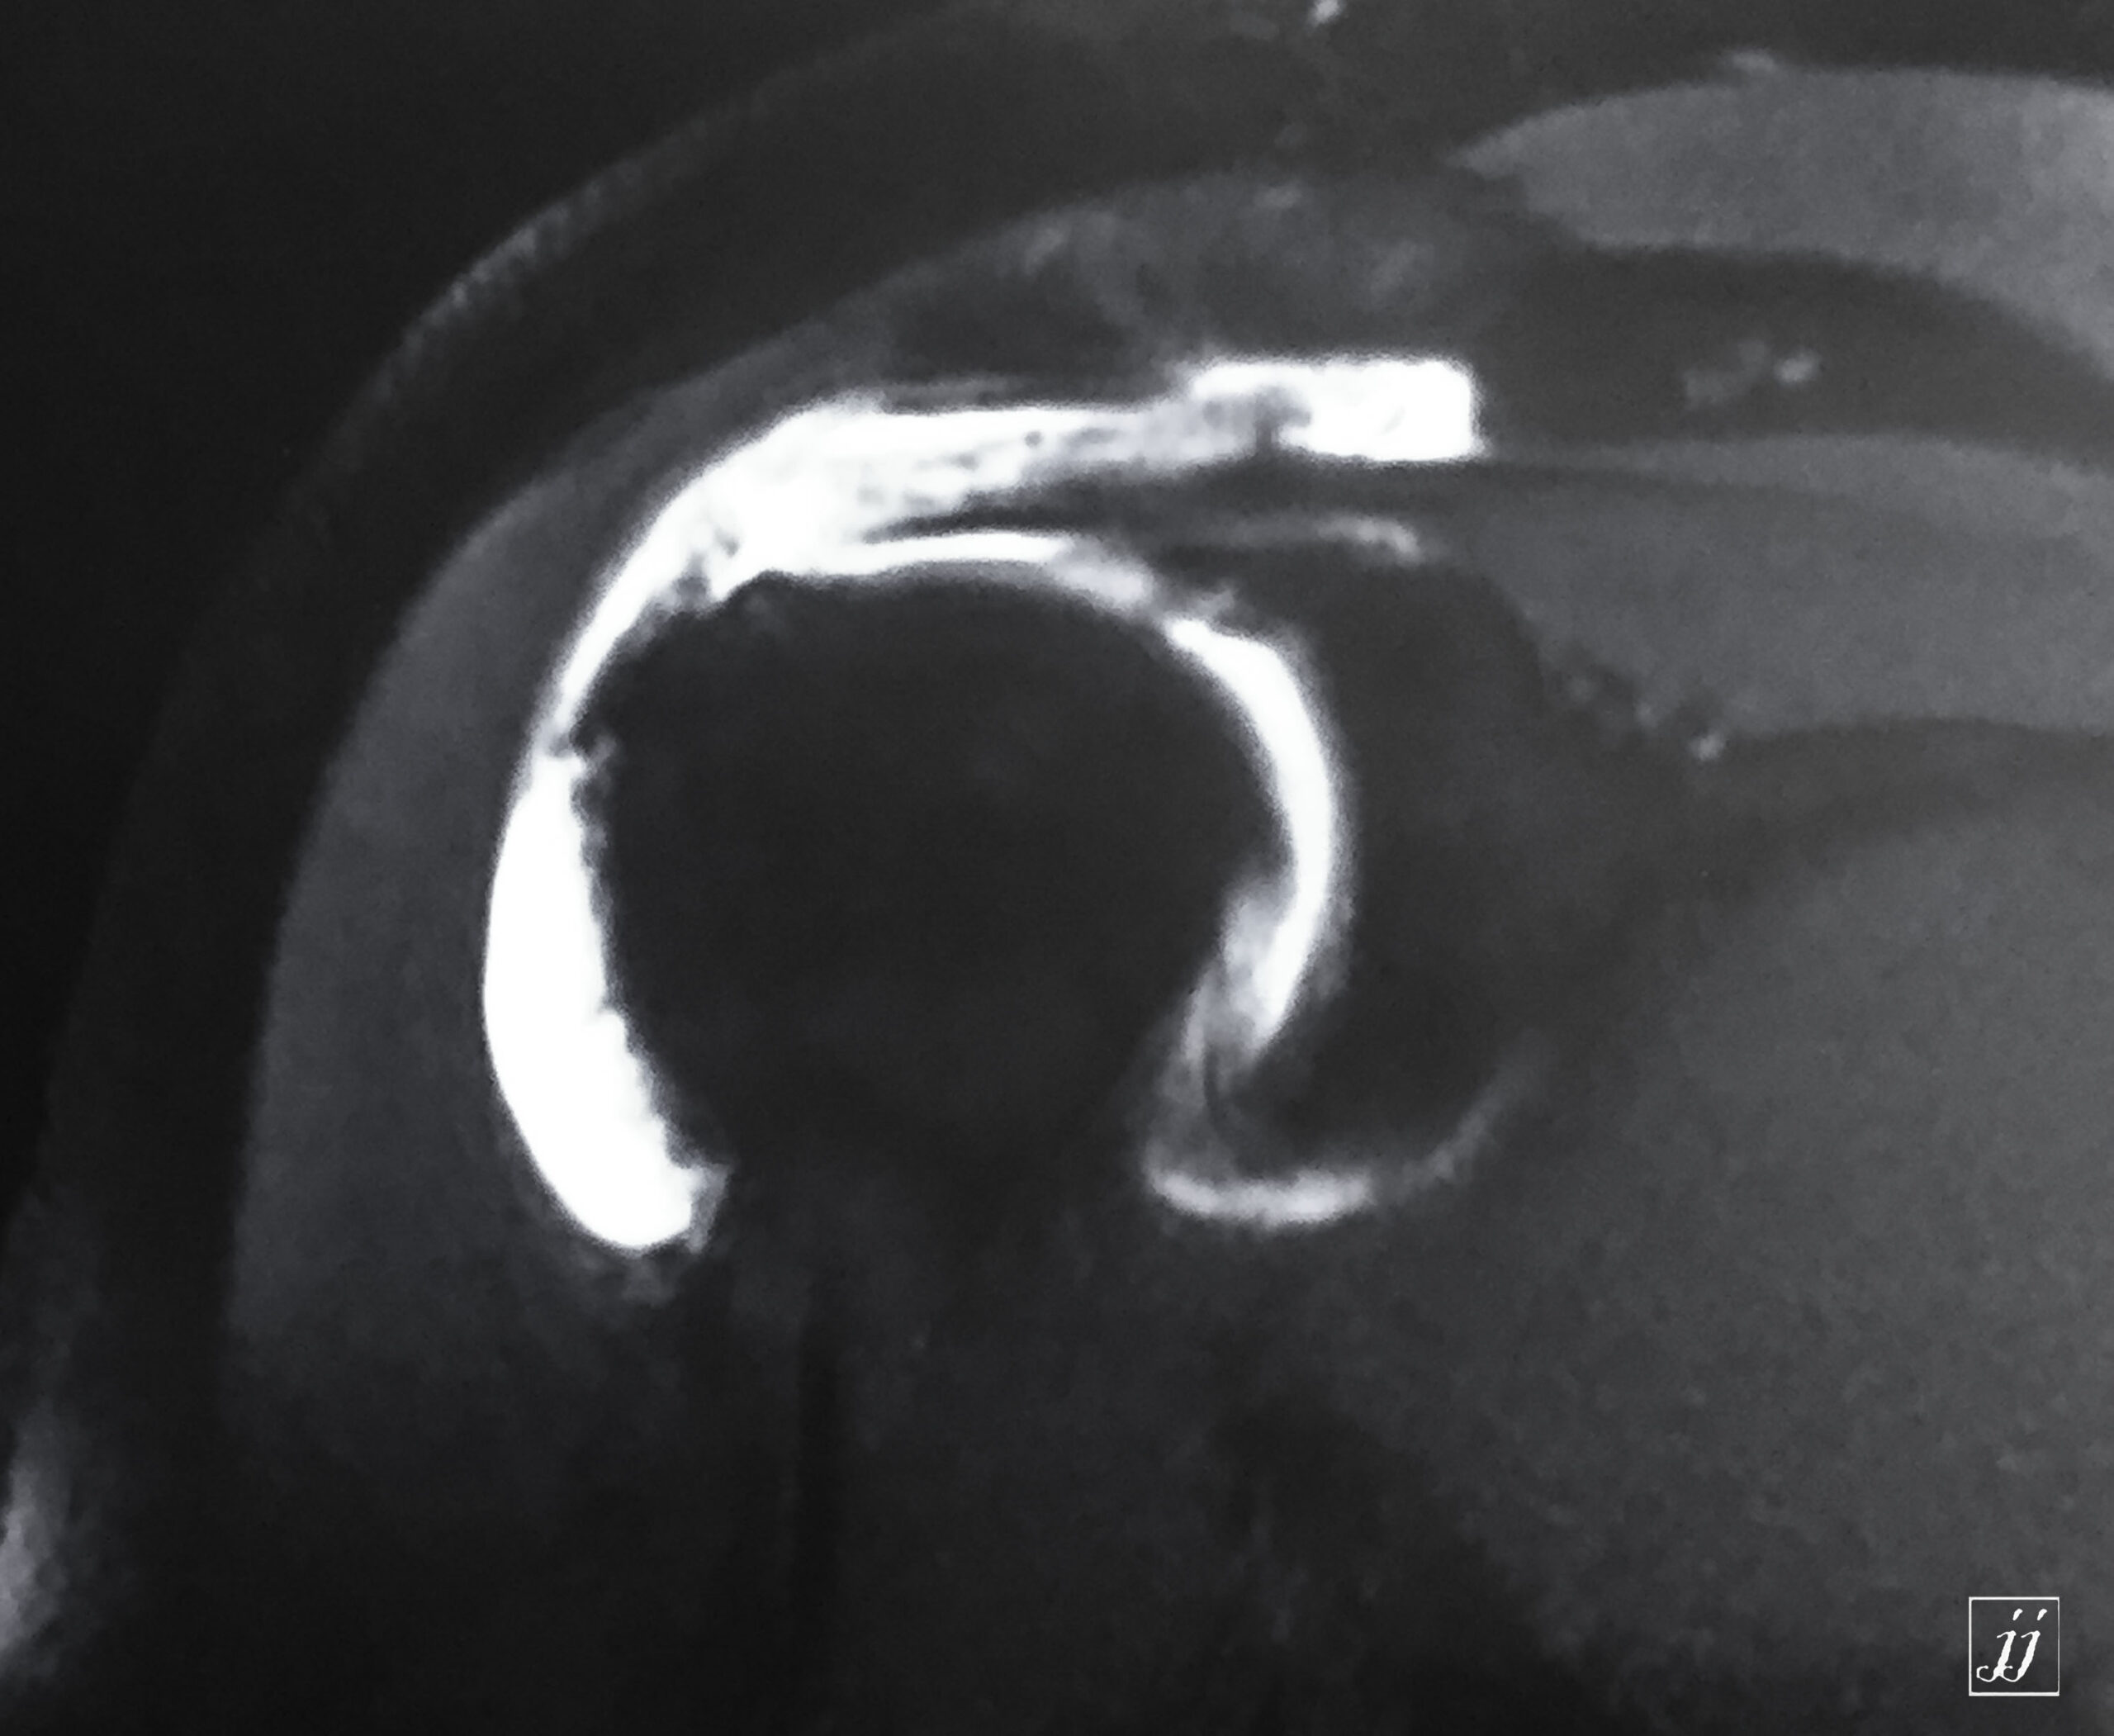

MSK- right pelvic floor muscular rupture and abnormal signal of right sacrum and pubic fracture (2)